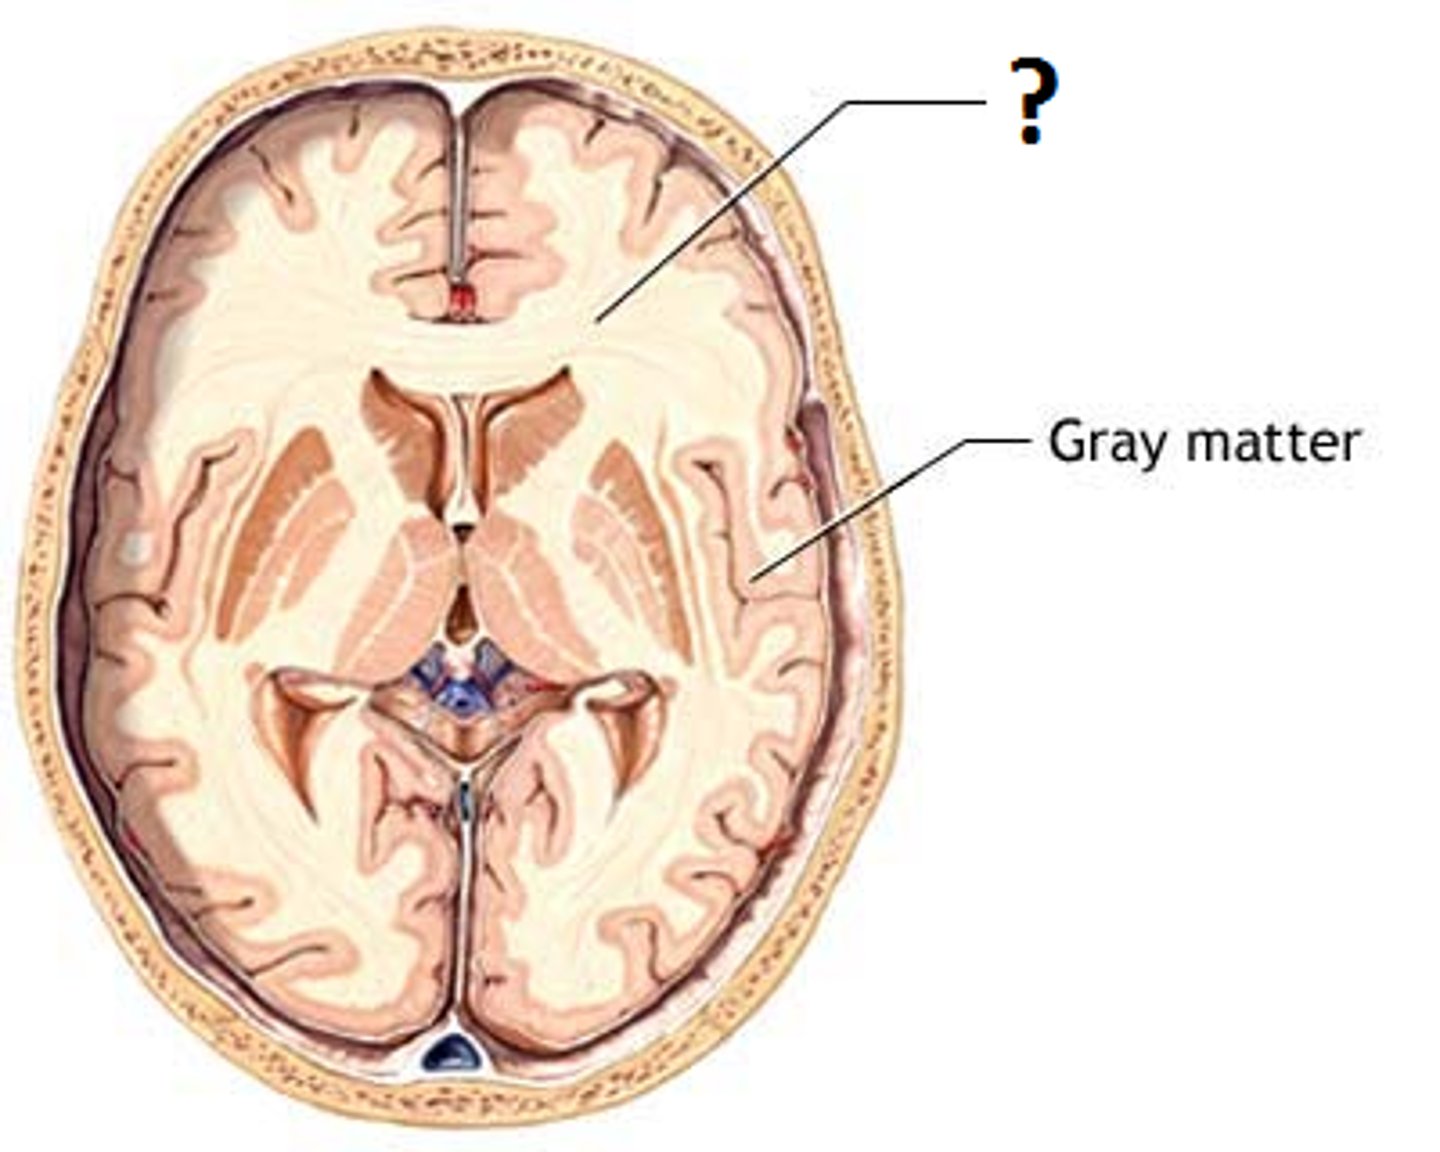

cerebral cortex

cerebral white matter

basal nuclei (cerebral nuclei)

right and left lateral ventricles

third ventricle